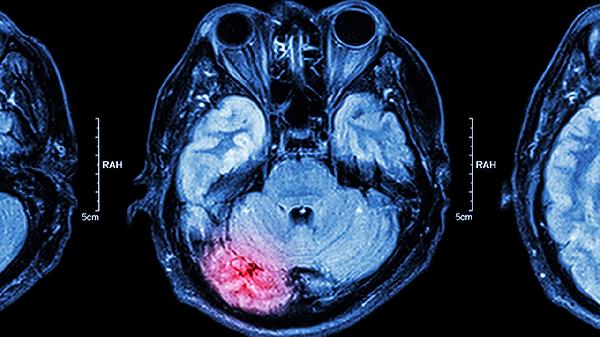

使用醒脑安神片期间应避免辛辣刺激性食物,保持规律作息。神经衰弱患者可配合适度运动如八段锦、散步等调节身体机能。长期失眠或头痛反复发作需及时到神经内科就诊,排查脑血管疾病、焦虑抑郁等潜在病因。